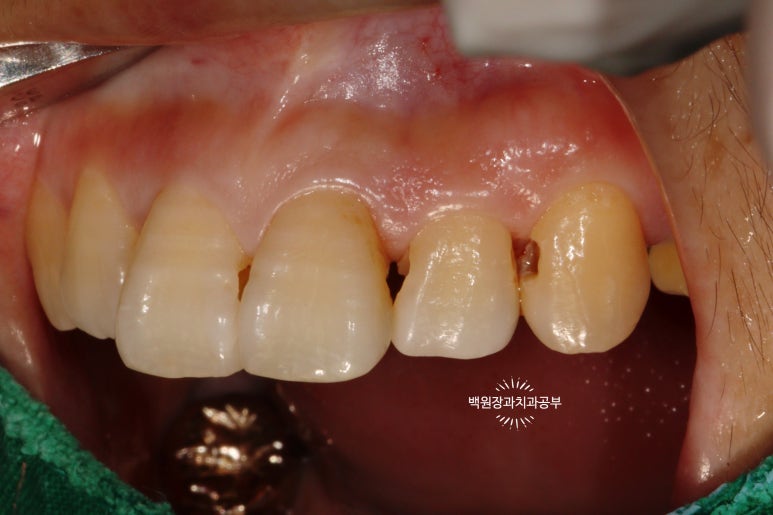

더 확실하게 보여드리기 위해 고개를 살짝 돌려서 보면..

고개를 돌려서 보면 인접면 충치를 더 잘 확인하실 수 있습니다!

집에서 확인해 보실 때도 고개를 돌려서 보셨었겠죠?

치과의사만 볼 수 있는 치아 뒷면 !!

사실 자기 앞니의 뒷면을 본 다는 것이 쉽지는 않습니다만..

치과의사는 뒷면을 볼 수 있습니다 !!!

딱 보아도 충치가 있는 걸 아실 수 있죠?

까맣게 보이는 부위들이 치아 옆면의 충치들입니다.